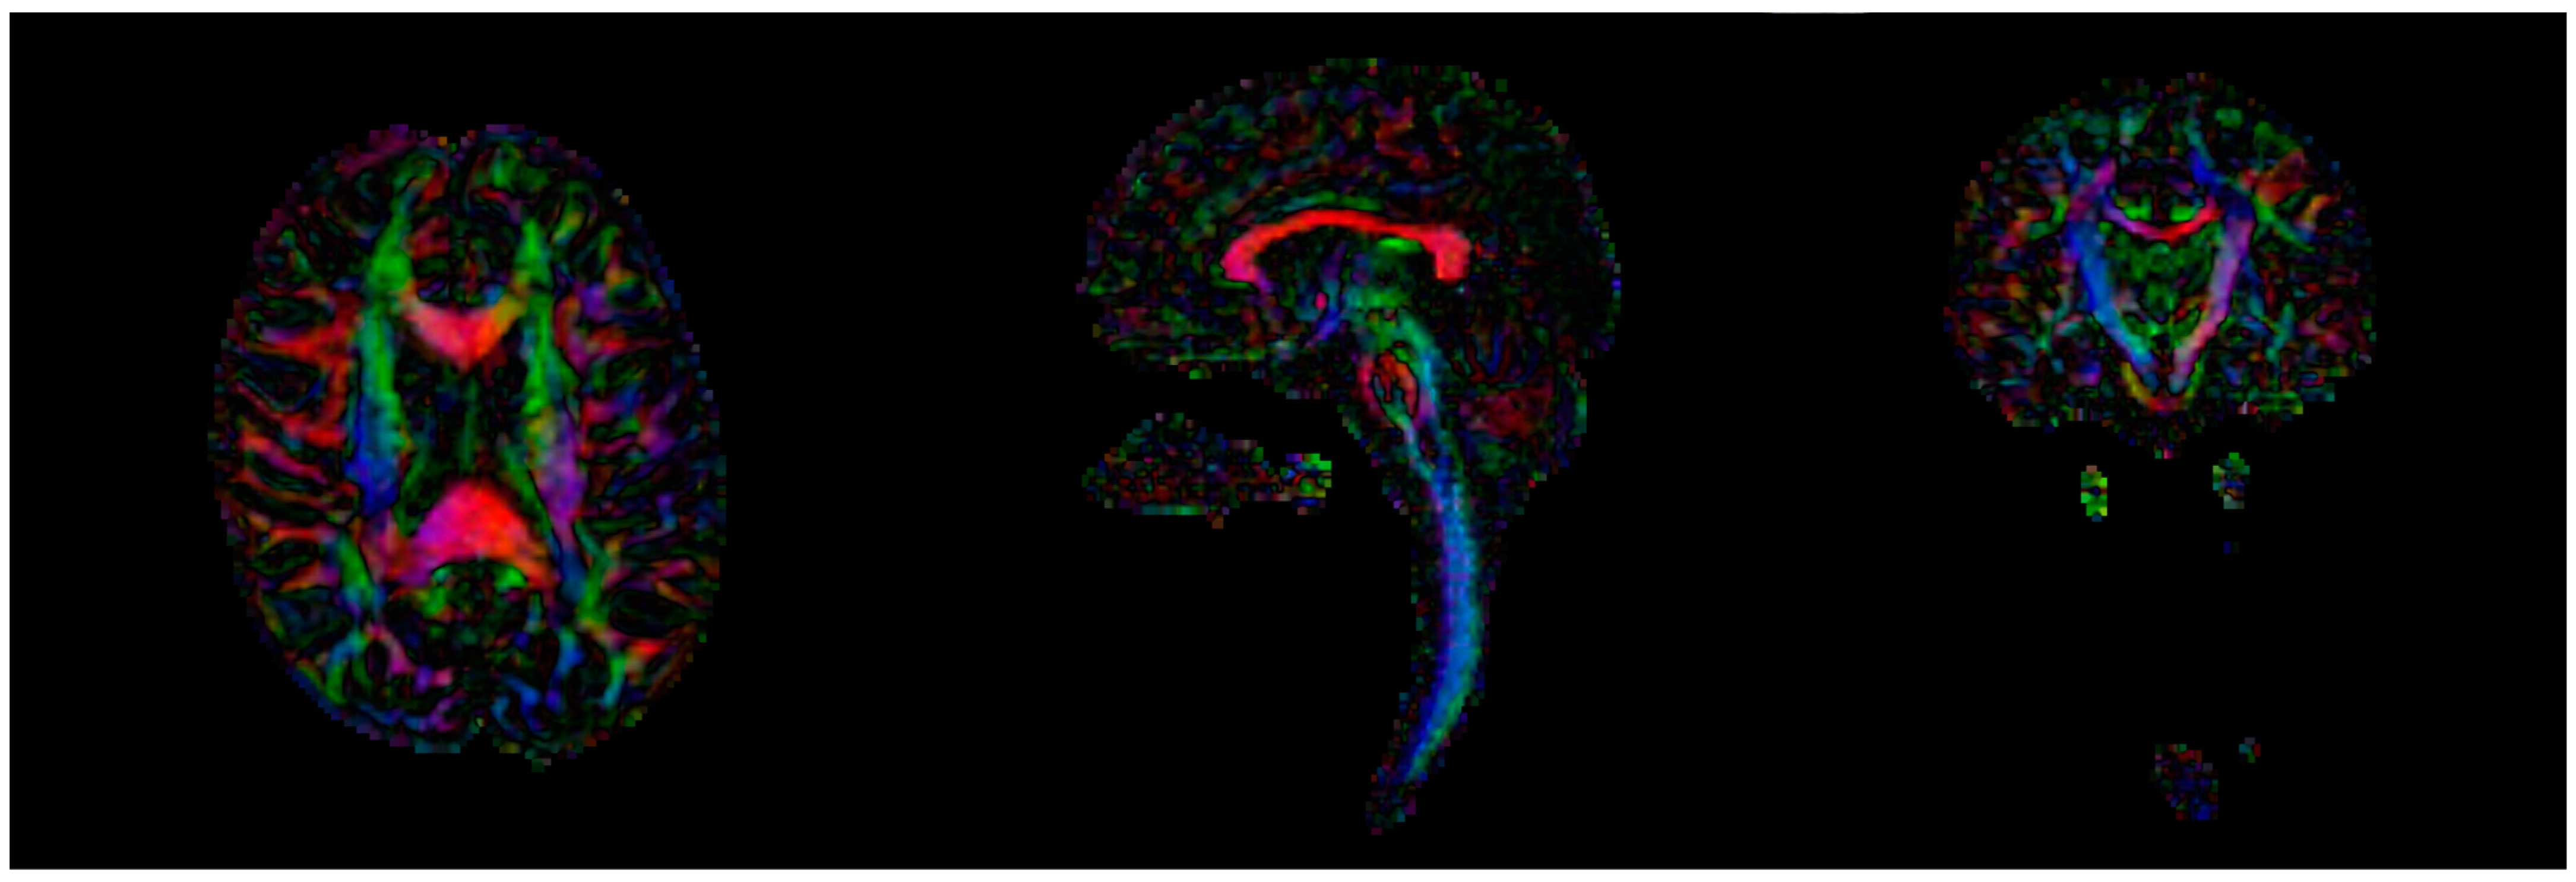

2.1. Magnetic Resonance Imaging (MRI)

2.1.1. Image Processing